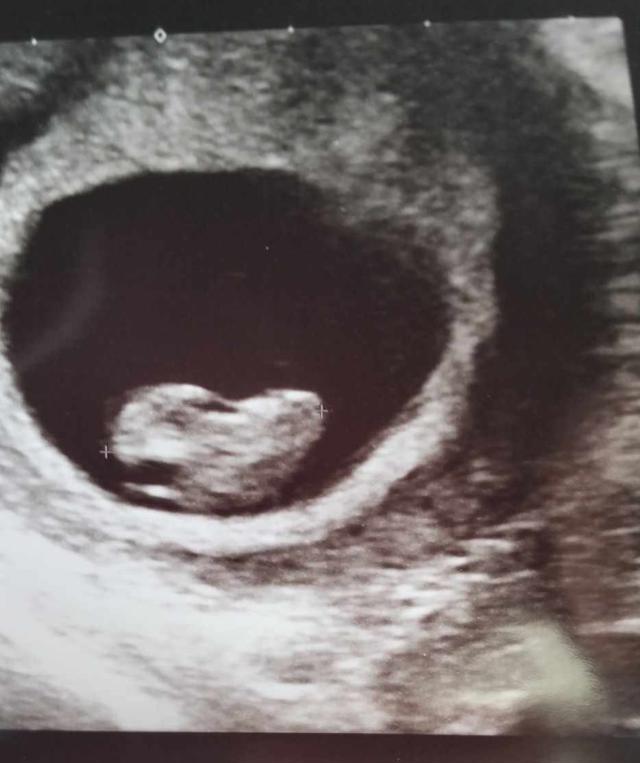

I'm pregnant now ❤️ because of everything you all have put in 🙏🏽❤️

Thank you Soo much from all of my heart , I could not be pregnant right now if it wasn't for you . I'm eternally grateful.

We wanted to give you a quick update on Stacey and let you all know that she managed to get to Greece last month and have IVF treatment, which has resulted in pregnancy 🎊 We are all over the moon, however, it is still very early days, and everyday of pregnancy will be immensely stressful and scary until she gets to hold her baby in her arms. She wanted us to thank you all from the bottom of her heart because without your help, she wouldn't have had the chance to try again. And honestly, it gave her the hope to carry on. Her heart will forever be broken from losing Elijah, and she is still fighting his case because there was no reason for his death other than pure incompetence. We would appreciate all the thoughts, prayers, good vibes, hopes and wishes for the rest of Stacey's pregnancy, and just thank you, thank you, thank you for all you have done! From all of Stacey's Whanau ❤️